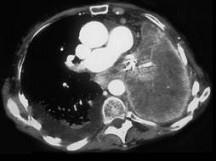

问题 男,68岁,咳嗽,咯血2月余,有40余年吸烟史,请结合影像学检查,选出最可能的诊断 ( )

选项 A、肺脓肿 B、纵隔畸胎瘤 C、肺癌 D、肺结核 E、肺囊肿

答案 C